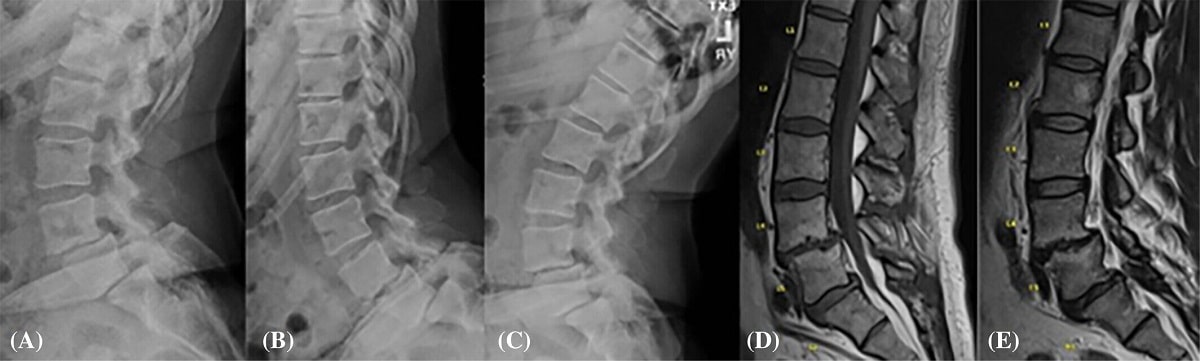

Результаты магнитно-резонансной томографии пациентки с дегенеративным спондилолистезом пояснично-крестцового отдела позвоночника / © Khaled Aboushaala et al., JOR Spine

Кишечный микробиом повлиял на позвоночник   Медицина

Микробиом, то есть разнообразие и соотношение микроорганизмов в кишечнике, критически важен для здоровья и может стать причиной болезней разных органов. Международная команда ученых обнаружила, что большое количество некоторых кишечных бактерий …